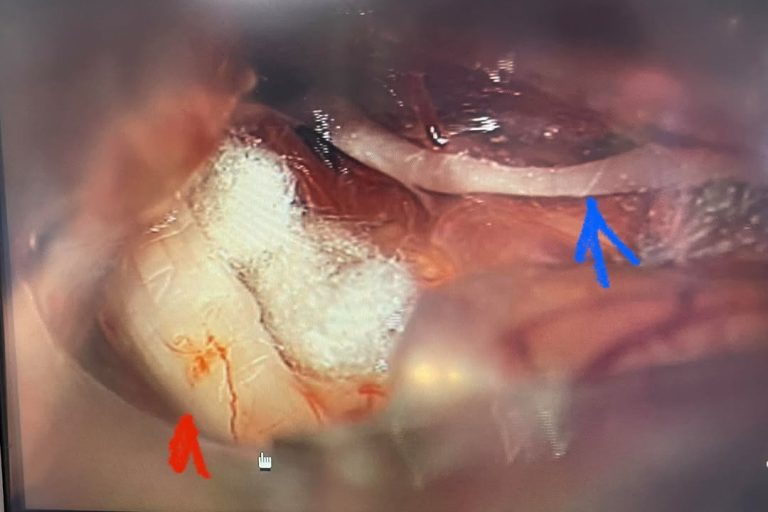

Meet Lin Sanders—a true inspiration of resilience and determination! Part 1 Lin underwent a complex two-level lumbar fusion at Texas Neuro-Spine Surgery. The procedure involved an anterior lumbar interbody fusion (ALIF) at L3-4 and L4-5, followed by laminectomies and pedicle screw instrumentation at the same levels. These surgeries were performed to help address her back…